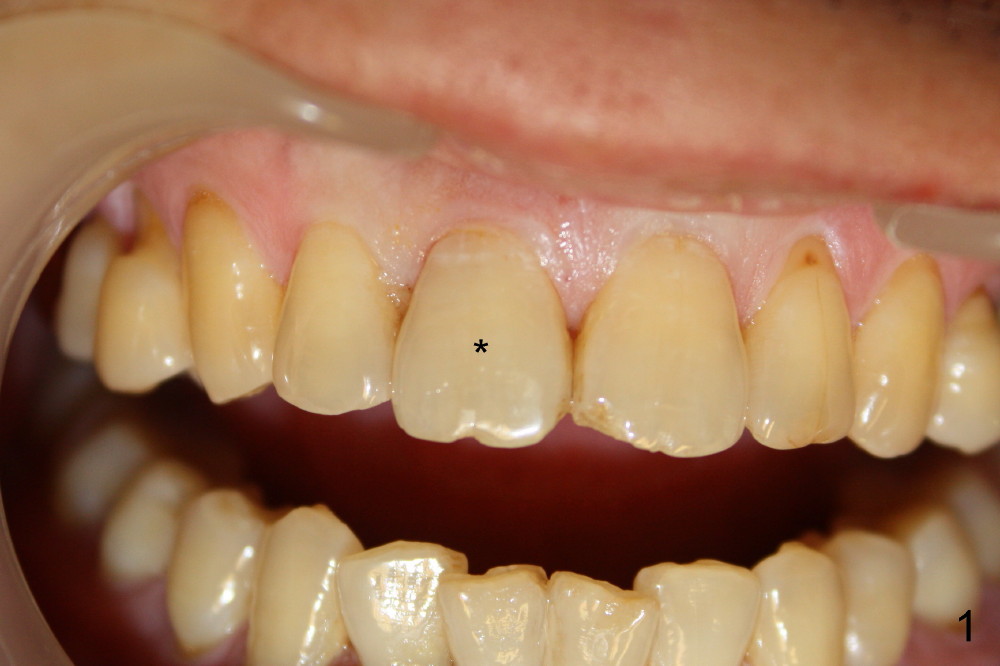

A 55-year-old man has severe pain on the upper right central incisor (Fig.1 *) after biting on a piece of bone. PA confirms crown fracture (Fig.2 <), extending subgingivally (Fig.3 >>). Osteotomy forms using a 2 mm pilot drill and 2.5-3.5 mm reamers (Fig.4). A 5x17 mm Tatum tapered implant is placed, autogenous bone placed in the buccal gap, sutures placed for wound approximation and 3.5 mm 20º angled abutment installed (Fig.5). An immediate provsional is fabricated (Fig.6), cemented and splinted (Fig.7).,